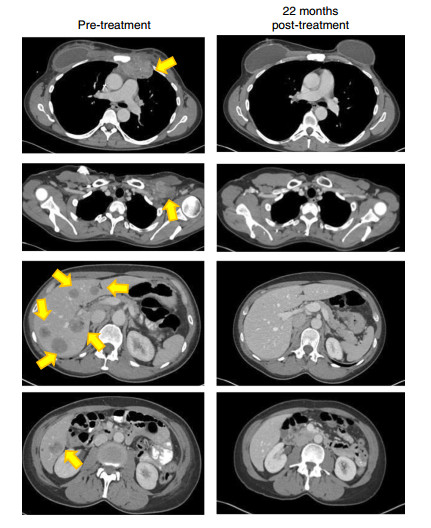

当900亿个免疫细胞被输回患者体内后,奇迹发生了。在6个月的第一次随访时,这位乳腺癌患者的肿瘤正在逐渐缩小;在治疗后的22个月,医学影像上显示,患者胸腔内的肿瘤都消失了

黄色箭头表示肿瘤已消失了

图:参考资料[5]